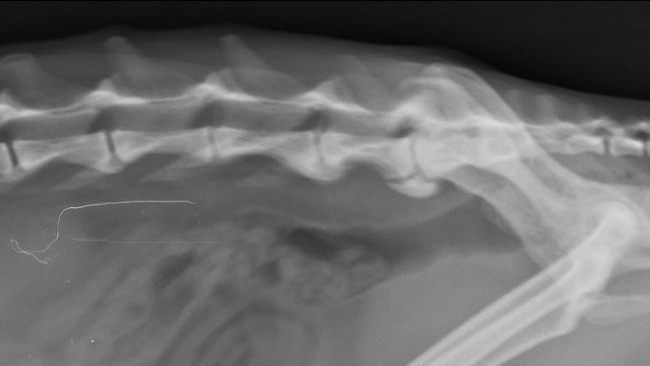

Niunia jest rezolutną kotką, pełną życia i radości w oczkach. Uwielbiała sie bawić z innymi domownikami i towarzyszącymi jej innymi kotami domowymi. Niestety od jakiegoś czasu jej stan zdrowia mocno się pogorszył. Straciła ochote na zabawę, przeszła zabieg usuwania kamieni z pęcherza - ratujemy naszą kicie na wszystkie możliwe sposoby. Po zabiegu odzyskała chęć na zabawę, zaczęła się wspinać, wypróżnianie nie było już takie trudne dla niej. Jednak z dnia na dzień jej stan zdrowia się pogorszył, a po świętach Bożego Narodzenia doprowadził do tego, że kicia nie jest w stanie samodzielnie chodzić.. Nagle kicia przestała chodzić. Po konsultacji weterynaryjnej wiem, że tak naprawde ból kręgosłupa nie pozwala jej normalnie korzystać z życia. Niunia ma stwierdzone zwyrodnienie kręgosłupa.. potrzebny jest rezonans magnetyczny, który jest mega kosztowny i być może po tym badaniu zostałaby zakwalifikowana na operacje kręgosłupa.. 😔💔

Od kilku lat kicia zmaga się z chorobą nerek, ale mimo doskwierających problemów moczowych jej wyniki badań są bardzo zadowalające. Nie można jednak tego powiedzieć o jej kręgosłupie. Kotka ma 10 lat więc tak naprawdę ma przed sobą jeszcze kilka lat życia, niestety bez kosztownego zabiegu czeka ją wózek inwalidzki..

Dziś nie jest w stanie zrobić nawet dwóch kocich kroków, nie jest w stanie usiąść, ponieważ od razu się przewraca. Wchodzenie na wysokość i korzystanie z kuwety jest nie wykonalne bez przewrócenia się. Oprócz tego towarzyszy jej zanik mięśni skokowych. Próbujemy tego uniknąć masażami i rehabilitacją domową.